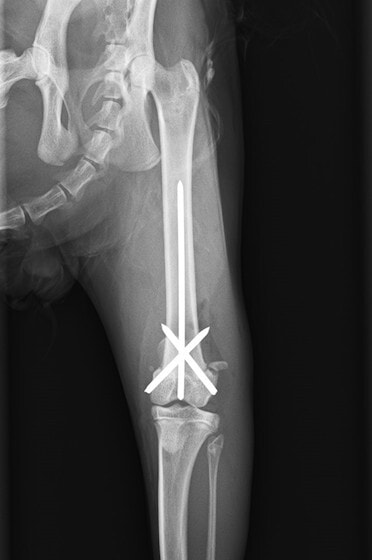

症例3:キルシュナーワイヤーのピンニングによる整復

ペルシャ猫 11ヶ月齢 雄

他院にて左大腿骨遠位の成長板骨折(salter-harrisⅠ型)が認められており、治療相談を目的として来院。当院にて、キルシュナーワイヤーを用いたピンニングにより骨折部位の整復を行いました。術後の経過は良好で、現在も経過観察中です。

術前レントゲン

術後レントゲン